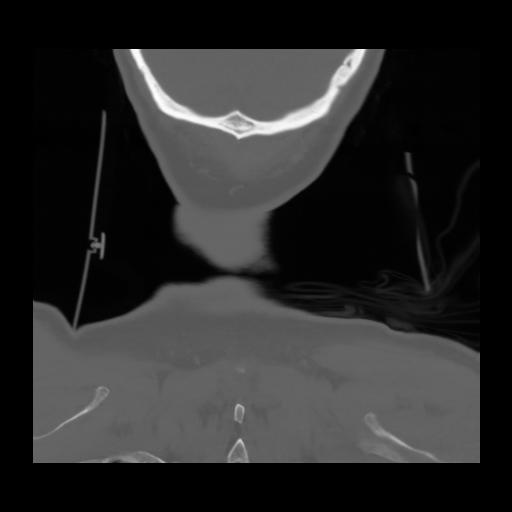

13 P.BLANDAS,,Coronal,2.000,P.BLANDAS,Coronal,